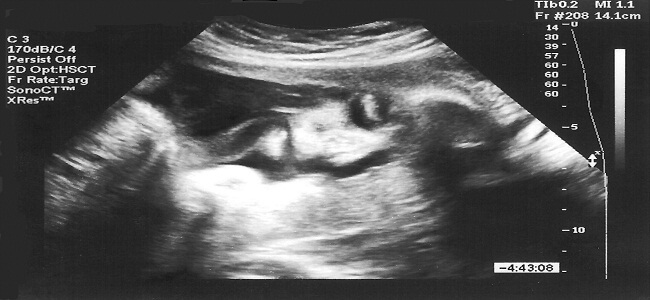

Lekarz przebada ci piersi, płuca, serce, określi wagę ciała i ciśnienie krwi, co na późniejszym etapie cięży będzie służyło do porównania. Poza tym ginekolog zbada twoje narządy rozrodcze, określi wielkość i położenie macicy. Kolejne badania, takie jak USG pomogą również w przebadaniu rozwoju płodu. Poza tym z pewnością zleci ci inne badania, by móc monitorować przebieg ciąży.

Jak duży jest dzidziuś?

W piątym tygodniu zaczyna rozwijać się oś dziecka, która w przyszłości będzie stanowiła jego kręgosłup. Poza tym rozpoczyna tworzyć się układ nerwowy naszego maleństwa, mózg i zaczątki oczu. Zarodek ma już mały układ naczyniowy, w obrębie którego zalążek serca zaczyna przepompowywać krew. Pod koniec 7 tygodnia ma on już około 12 mm długości. Zaczynają tworzyć się narządy wewnętrzne dziecka, chociaż nie pełnią one jeszcze swojej roli. W dziewiątym tygodniu maleństwo ma już około 2 cm. Wyodrębnione są już kończyny, żebra i kręgosłup twardnieje, wykazuje on już wrażliwość na dotyk.